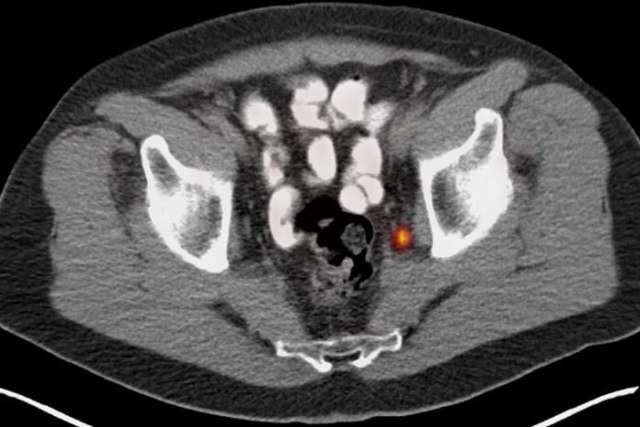

PSMA PET image.

PSMA PET image. Courtesy of Jeremie Calais, UCLA.

The tool, known as prostate-specific membrane antigen PET imaging, or PSMA PET, provides prognostic information before treatment begins that can predict if the patient will have a high risk for the cancer returning after surgery.